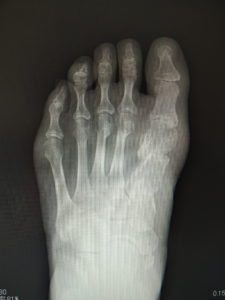

(図5)

手術前 手術後4年

(図6)

手術前 手術後

(図7)